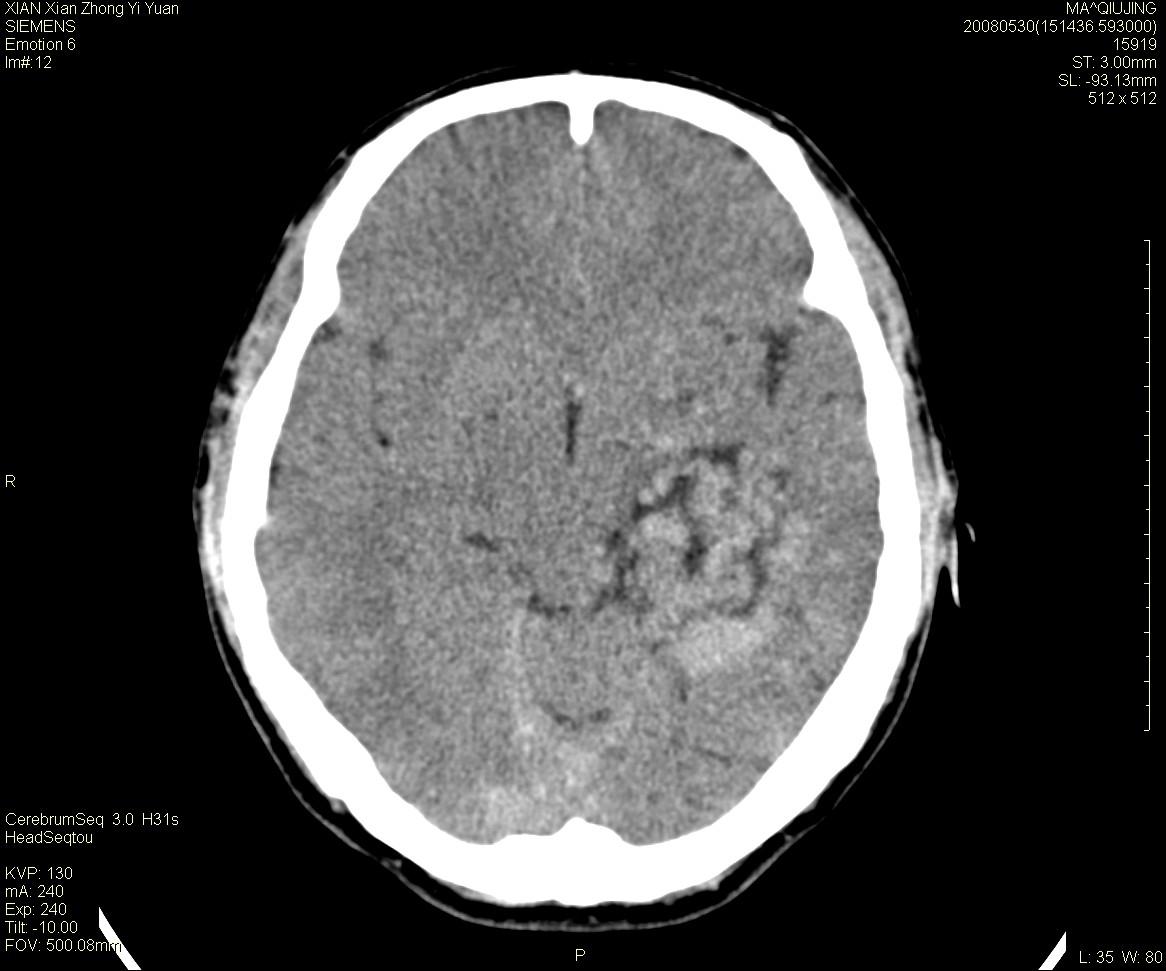

标题: CT13768:少见病例,血管畸形。

患者m47,头晕数年,没给强化,让做dsa去了。

avm

第一感觉:avm,但其中更低密度区不清楚,好像有脂肪密度,胆脂瘤破裂?

avm,低密度区应该是以前出血过的液化灶

血管畸形,支持,如果增强扫描,则可见粗大,迂曲血管团。

脑血管畸形可能性大 但应与血管肿瘤相鉴别